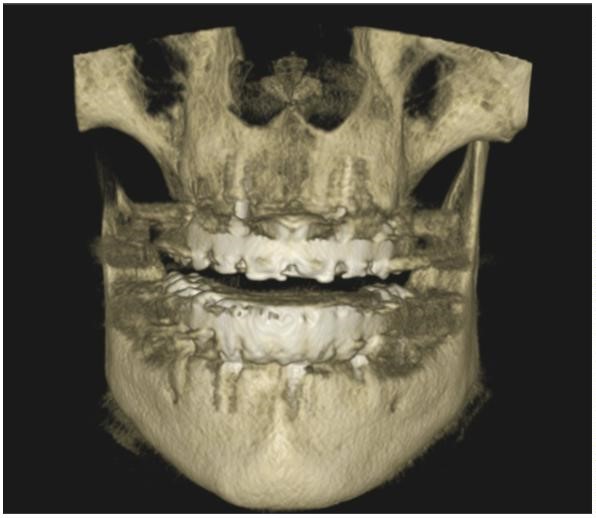

Para la planificación de la colocación de los implantes, la exploración clínica se complementa con la radiológica. La Radiografía Panorámica (OPG) (Figura 3) y la Tomografía Axial Computarizada (TAC) (Figura 4) nos permiten obtener la medición de los implantes y su punto de colocación.

Además, la Tomografía Computarizada de Haz Cónico (CBCT) nos informa sobre la cantidad y calidad ósea prequirúrgica. (Figura 5)

Una vez realizado esto, se establece el protocolo de revisiones de 3-6 meses tras la cirugía para comprobar la osteointegración de los implantes y que todo siga su curso normal. Se realiza un nuevo CBCT para su comprobación.

Una vez terminada la prótesis final y colocada en la boca del paciente (Figura 13), se le dan instrucciones de higiene y mantenimiento de implantes y prótesis. Se le da importancia a las revisiones periódicas para una buena evolución del tratamiento realizado. También se realiza un CBCT de control (Figuras 14 y 15).